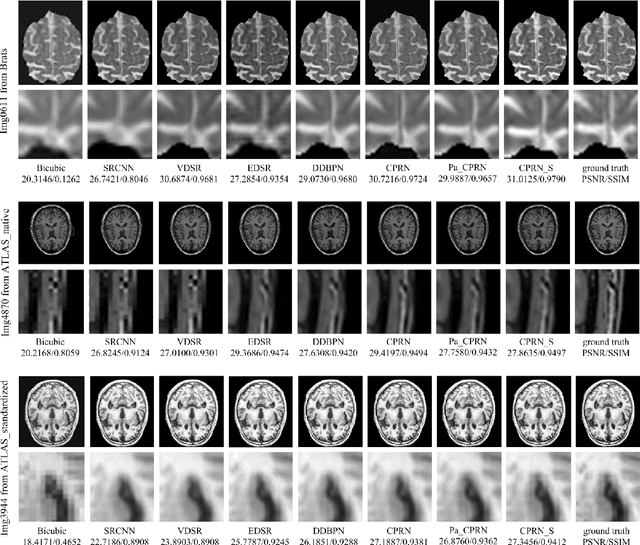

Abstract:Magnetic Resonance Imaging(MRI) has been widely used in clinical application and pathology research by helping doctors make more accurate diagnoses. On the other hand, accurate diagnosis by MRI remains a great challenge as images obtained via present MRI techniques usually have low resolutions. Improving MRI image quality and resolution thus becomes a critically important task. This paper presents an innovative Coupled-Projection Residual Network (CPRN) for MRI super-resolution. The CPRN consists of two complementary sub-networks: a shallow network and a deep network that keep the content consistency while learning high frequency differences between low-resolution and high-resolution images. The shallow sub-network employs coupled-projection for better retaining the MRI image details, where a novel feedback mechanism is introduced to guide the reconstruction of high-resolution images. The deep sub-network learns from the residuals of the high-frequency image information, where multiple residual blocks are cascaded to magnify the MRI images at the last network layer. Finally, the features from the shallow and deep sub-networks are fused for the reconstruction of high-resolution MRI images. For effective fusion of features from the deep and shallow sub-networks, a step-wise connection (CPRN S) is designed as inspired by the human cognitive processes (from simple to complex). Experiments over three public MRI datasets show that our proposed CPRN achieves superior MRI super-resolution performance as compared with the state-of-the-art. Our source code will be publicly available at http://www.yongxu.org/lunwen.html.